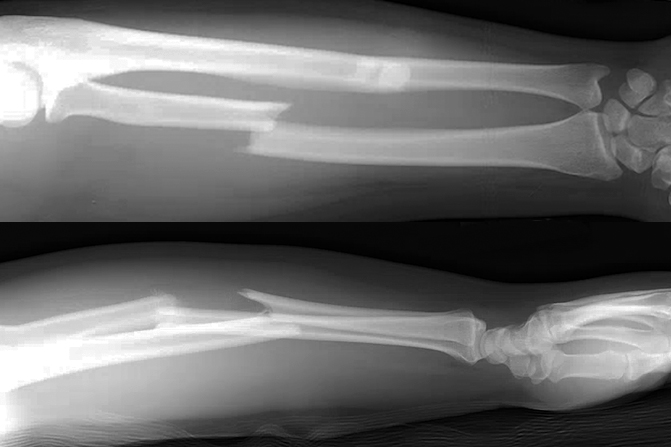

- Also known as a reverse Monteggia fracture or Piedmont fracture, the Galeazzi fracture is fracture of the middle to distal third of the radial shaft combined with a subluxation or dislocation of the DRUJ.8,11

- These injuries typically result from direct impact to the radius with forearm pronation. When a patient sustains a radial shaft fracture in the middle to distal third of the bone, suspicion should be raised for an associated DRUJ injury.1,8

Imaging11

- Radiology studies - X-ray

- Anteroposterior (AP) and lateral views are usually sufficient, but an oblique view may help to better classify the injury.

- If a coexistent injury is suspected, the distal wrist and proximal elbow should also be radiographed.